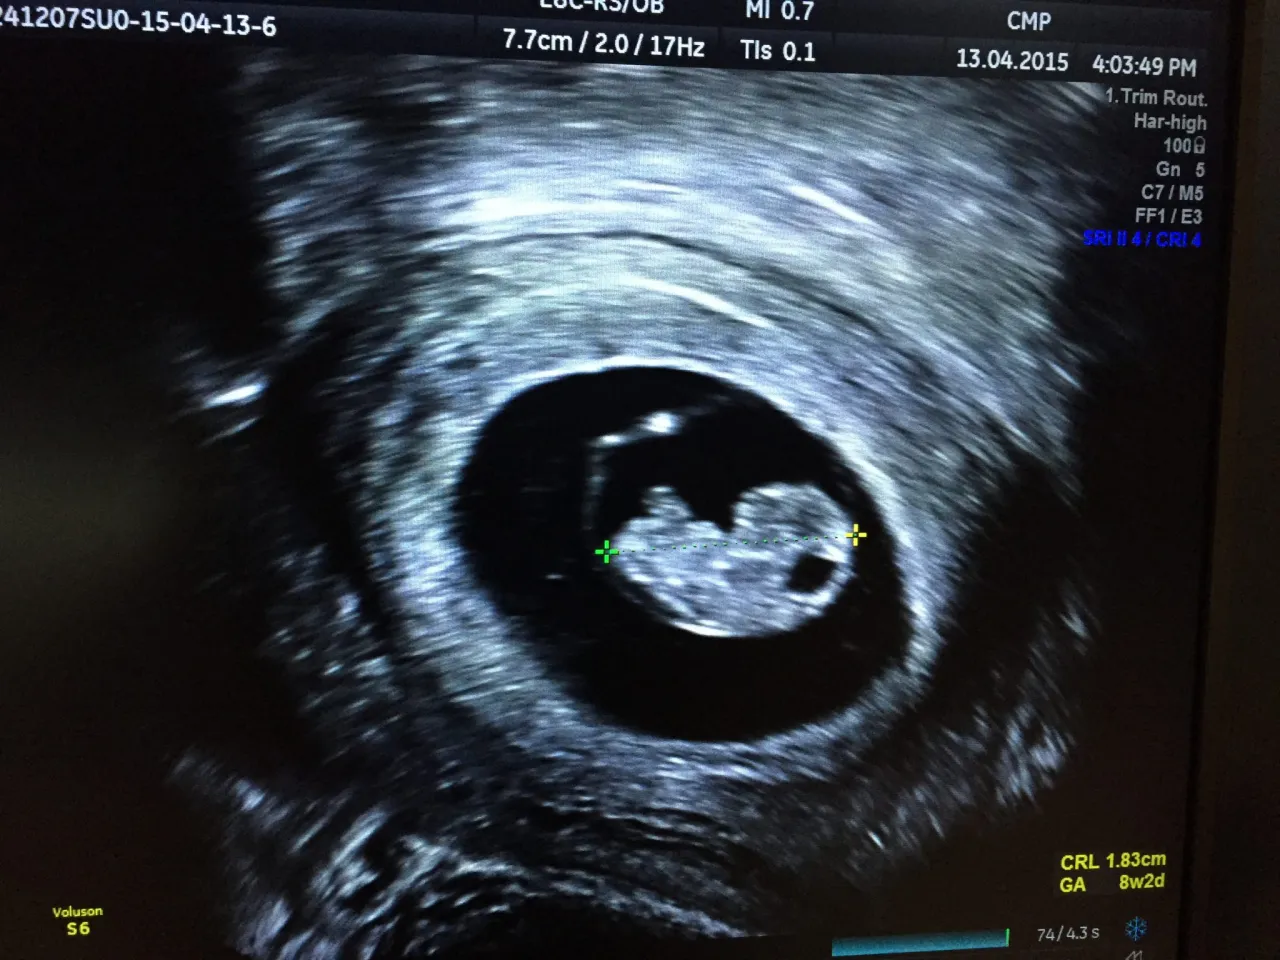

- Pierwsze badanie USG (6-12 tydzień) z pomiarem CRL jest kluczowe do weryfikacji i uściślenia wieku ciąży, zwłaszcza przy nieregularnych cyklach.

Pierwsze USG w ciąży: Jak pomiar CRL płodu uściśla Twój tydzień ciąży?

Pierwsze badanie USG, które zazwyczaj wykonuje się między 6. a 12. tygodniem ciąży, jest niezwykle ważne. W tym czasie lekarz dokonuje pomiaru długości ciemieniowo-siedzeniowej (CRL) płodu. Jest to odległość od czubka głowy do końca tułowia dziecka. Pomiar CRL jest najdokładniejszym sposobem na określenie wieku ciążowego, ponieważ w pierwszym trymestrze wszystkie płody rozwijają się w bardzo podobnym tempie. Dzięki temu wynik USG może uściślić, a nawet skorygować wiek ciąży obliczony na podstawie ostatniej miesiączki.

Zdarza się, że wiek ciąży obliczony na podstawie ostatniej miesiączki różni się od tego, co pokazuje USG. Jeśli ta różnica jest znacząca zazwyczaj ponad 5-7 dni to właśnie wynik badania USG jest uznawany za bardziej wiarygodny. W takiej sytuacji lekarz skoryguje przewidywany termin porodu na podstawie pomiarów z USG. Nie ma powodów do obaw, to jest normalna praktyka i świadczy o tym, że dbamy o jak najdokładniejsze datowanie Twojej ciąży.